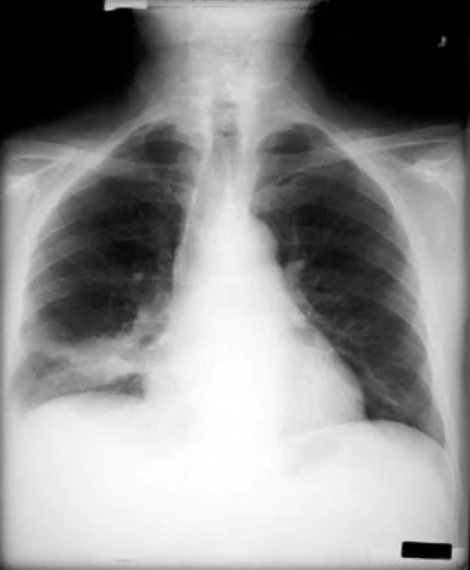

非小细胞肺癌。继发于左主支气管的支气管癌继发的完全左肺塌陷。